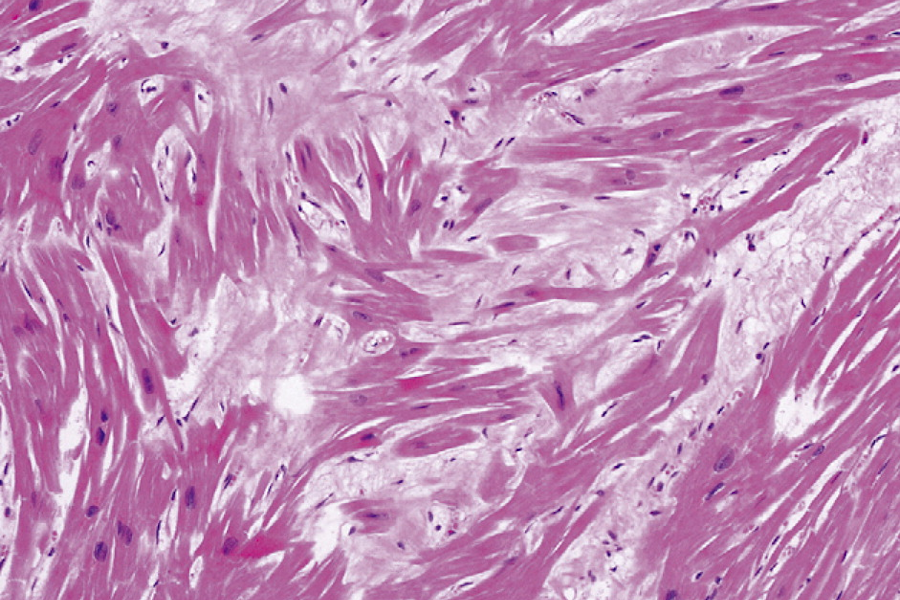

histologische Bilder

hypertensive Herzkrankheit

hypertensive Herzkrankheit

HFpEF = komplexes Krankheitsbild

- umfasst breites Spektrum unterschiedlicher Ätiologien

- Ausmaß wird durch Störung der Feinstruktur des Herzens erklärt